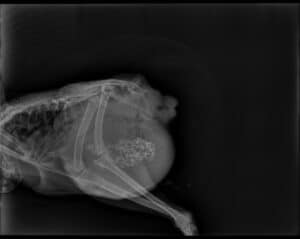

Radiographie d'une poule, il y a une masse importante dans le bas de l'abdomen, les petits points blancs sont des graviers dans son gésier